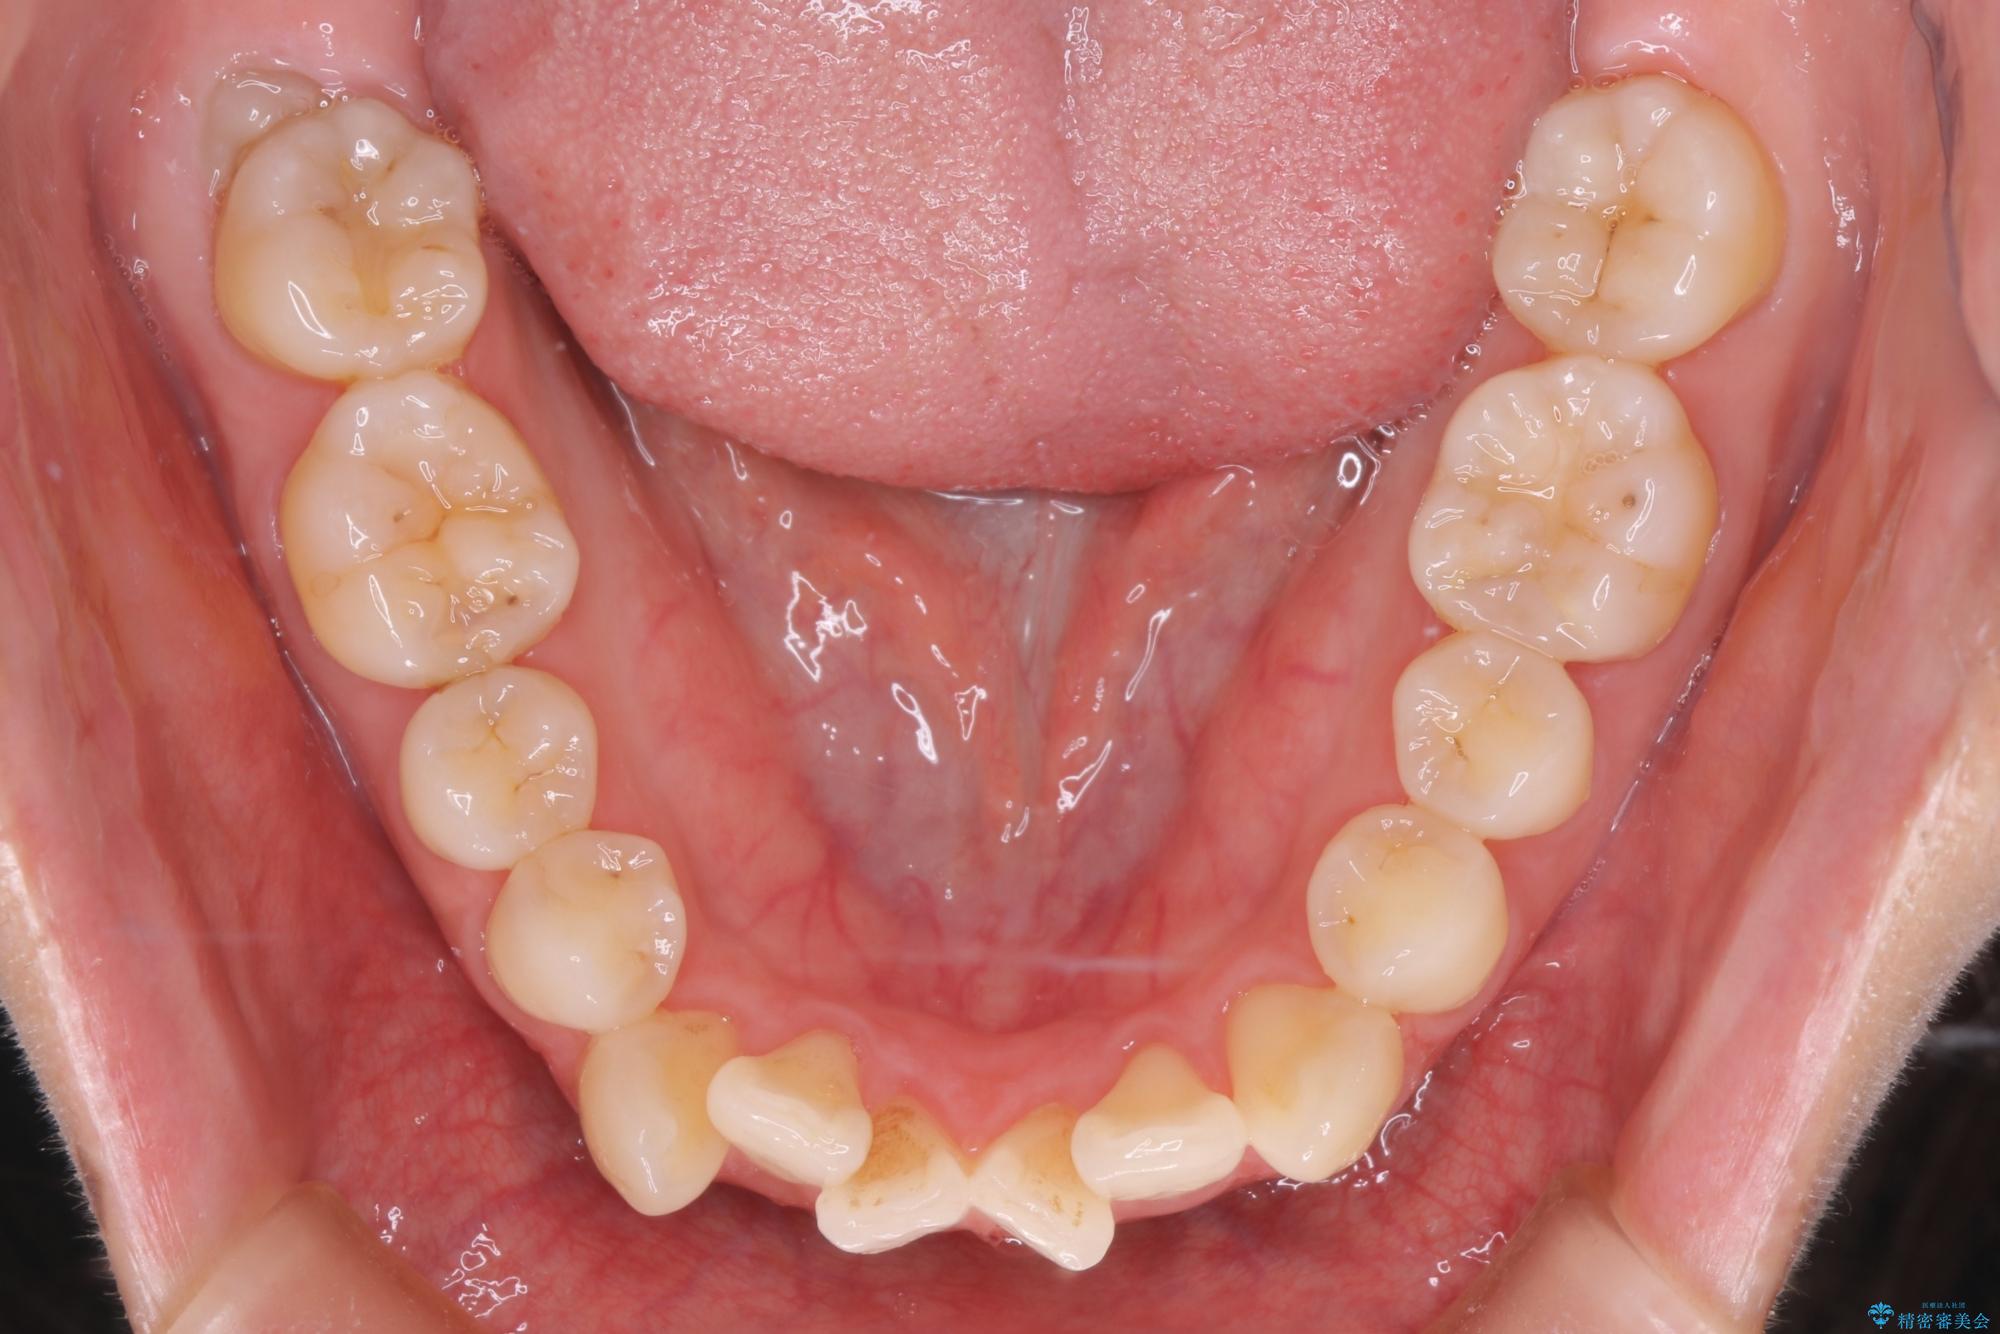

前歯のデコボコが改善され、噛みあわせも綺麗になりました。

歯肉退縮もなく、予定通りに治療を終えることができ大変ご満足いただけました。